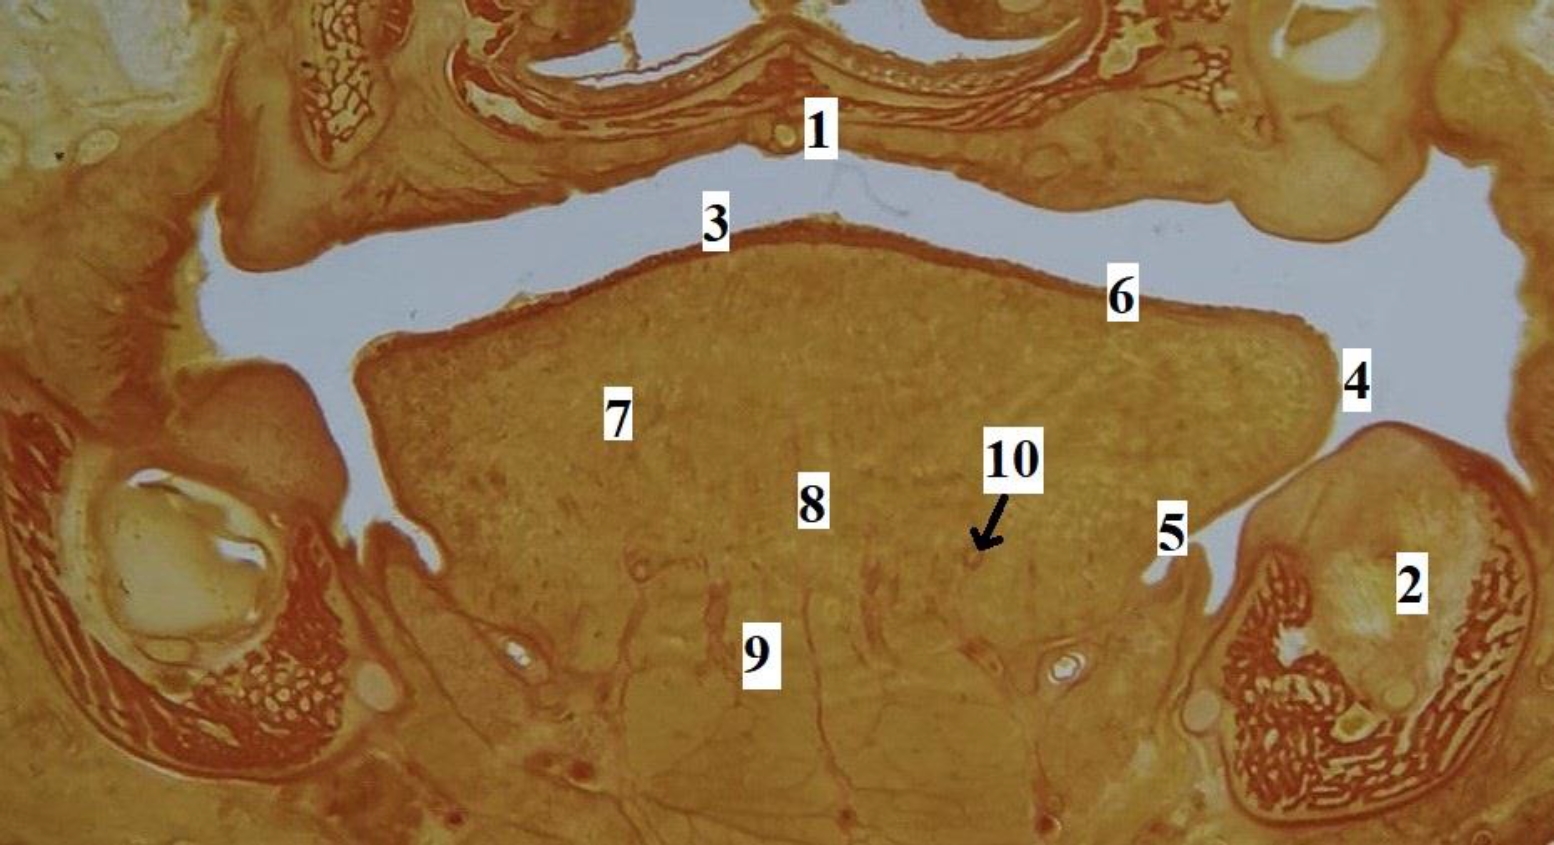

Рис. 3. Язык плода человека. Фронтальная гистотопограмма. Фото под микроскопом MicroOptix MX-1150, ок. ×10, об. 1. Возраст – 22 недели, пол мужской. Окраска по Ван – Гизону: 1 – твердое нёбо; 2 – нижняя челюсть; 3 – спинка языка; 4 – край языка; 5 – эпителий слизистой оболочки нижней поверхности языка; 6 – специализированный эпителий спинки языка; 7 – мышечные волокна поперечной мышцы языка; 8 – перегородка языка; 9 – мышечные волокна подбородочно-язычной мышцы; 10 – глубокая артерия языка

Рис. 2. Макропрепарат языка плода человека. Возраст – 17 недель, пол женский: 1 – слепое отверстие языка; 2 – пограничная борозда языка; 3 – спинка, предбороздовая часть тела языка; 4 – срединная борозда языка; 5 – край языка; 6 – верхушка языка; 7 – желобоватые сосочки языка; 8 – конусовидные, нитевидные, грибовидные сосочки языка

Язык человека в промежуточном плодном онтогенезе сформирован, макроскопически определяются все структурные элементы органа (рис. 2). На гистотопограммах визуализируется макромикроскопическая структура и микротопографические взаимоотношения мышц, сосудов, слизистой оболочки, стромального компонента языка (рис. 3). Линейные параметры языка, а также их описательная статистика представлены в табл. 2.